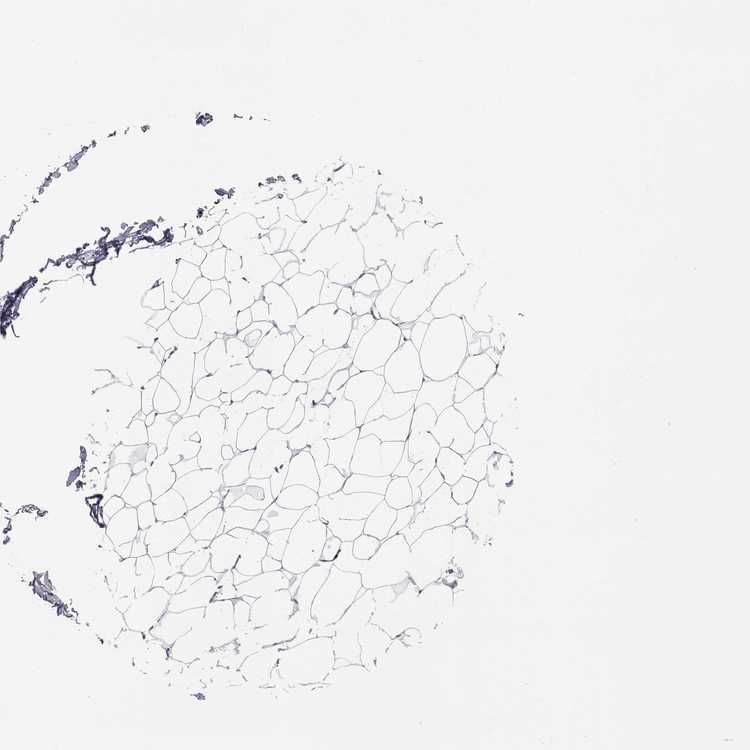

C6orf58